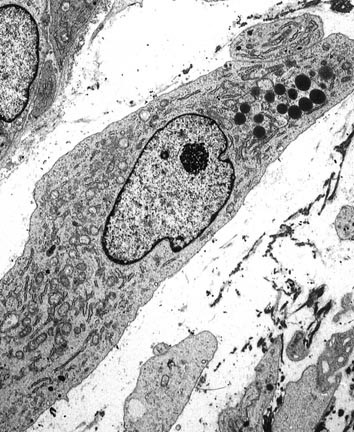

I was born in the city of Lynn, just north of Boston, the eldest of six children in a peripatetic military family for whom the only constancy was change itself (Fig. 4). My father was a charismatic Army surgeon who placed great value on education. He insisted that each of his children, whether son or daughter, receive a good education and, therefore, firmly supported my desire to attend Wellesley College, even though it meant considerable financial hardship for our family. I entered college intending to be an archaeologist, but by my junior year my interests began to change. I enrolled in a cellular biology course that featured no textbooks but rather a series of original scientific articles. My first assignment was to read and analyze the now-classic article by Marilyn Farquhar (the 1988 Maude Abbott Lecturer) and Nobelist George Palade on junctions in epithelial cells (1; Fig. 5). Struck by the beauty of the electron micrographs and the harmonious marriage of structure with function, I began to understand that my true love was to be in those sciences that enjoyed strong morphologic underpinnings.

Title page and electron micrograph from classic article by Farquhar and Palade (1) describing structure of junctional complexes in epithelial cells.

Concurrent with the plethora of clinical studies, pathologists continued to investigate the lineage of this tumor. On the basis of a large body of literature, it gradually became clear that the cells of the malignant fibrous histiocytoma possessed neither the ultrastructural nor immunophenotypic profile of the histiocyte but rather were more closely related to primitive mesenchymal cells or fibroblasts (33, 34, 35, 36). By immunohistochemistry, they lacked the usual enzymes (e.g., lysozyme; 34, 35) and surface markers (CD45, CD14,CD15; 35) associated with histiocytes and possessed, according to electron microscopy, prominent branching endoplasmic reticulum similar to fibroblasts (36; Fig. 18). Moreover, features often attributable to histiocytes, such as prominent primary and secondary lysosomes, which were observed in some cells in malignant fibrous histiocytoma, were easily explained by the phagocytic properties often acquired by neoplastic cells. However, study of the intermediate filaments in these lesions disclosed the unexpected presence of keratin, desmin, and even neural filaments (37, 38), raising the question of whether these unusual profiles reflected aberrant expression or a subtle form of differentiation not previously appreciated.